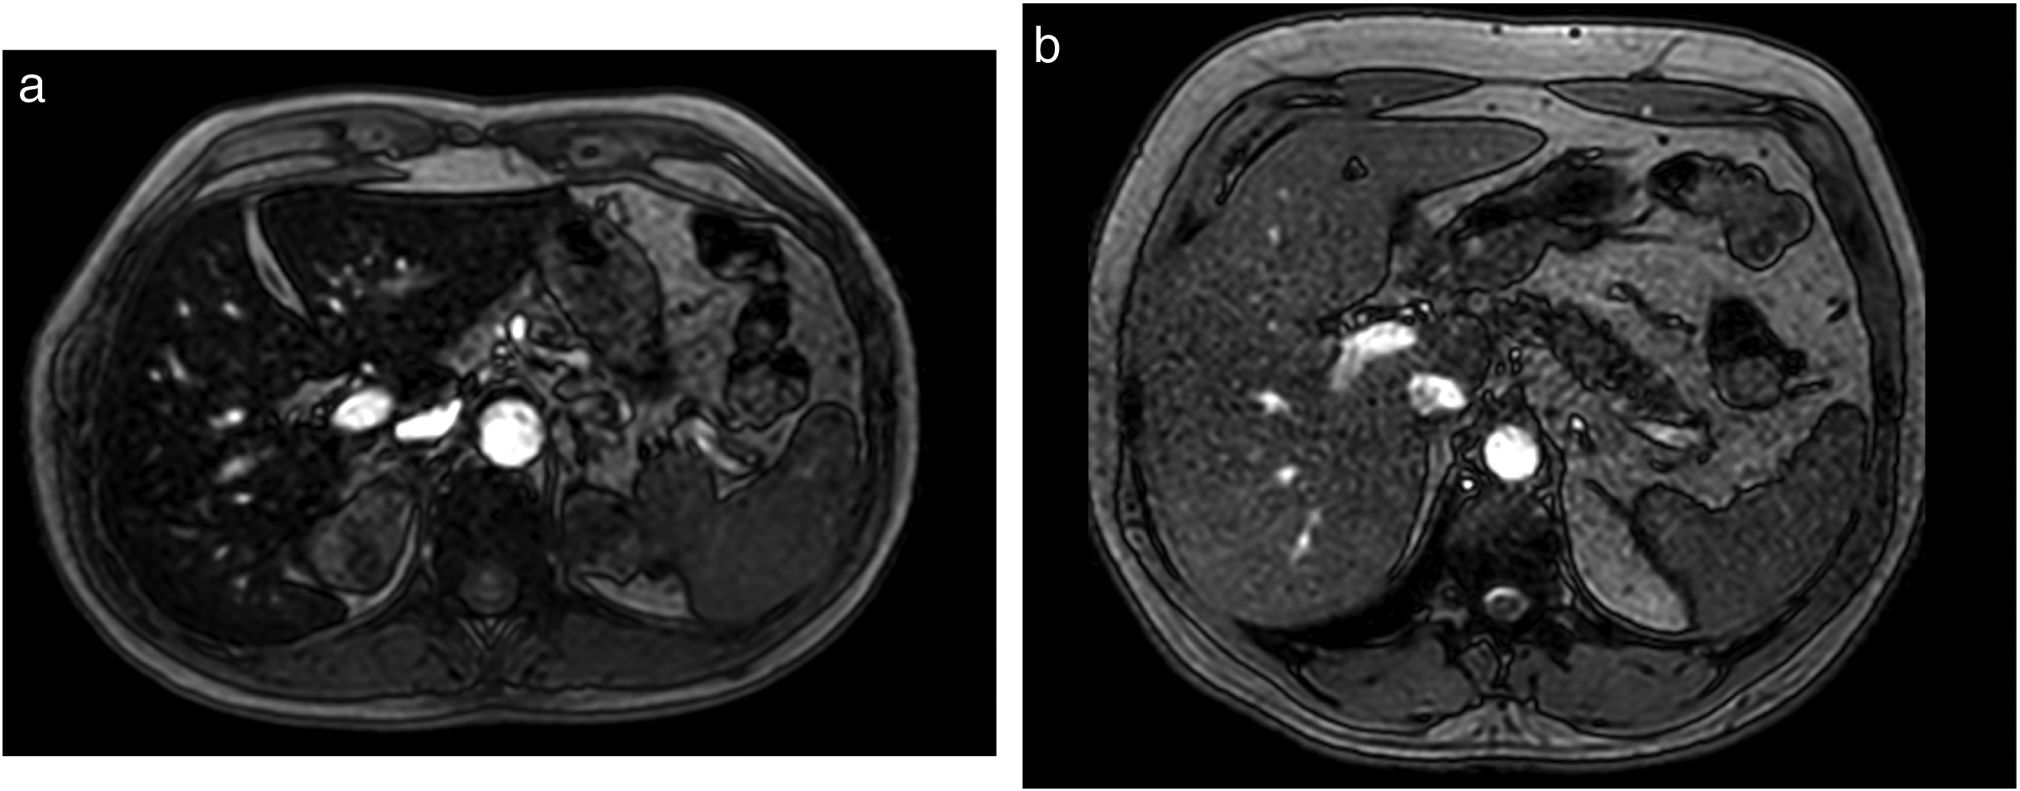

Iron overload refractory to phlebotomy in a patient with type 1 hereditary hemochromatosis

Sobrecarga férrica refractaria a flebotomías en un paciente con hemocromatosis hereditaria tipo 1